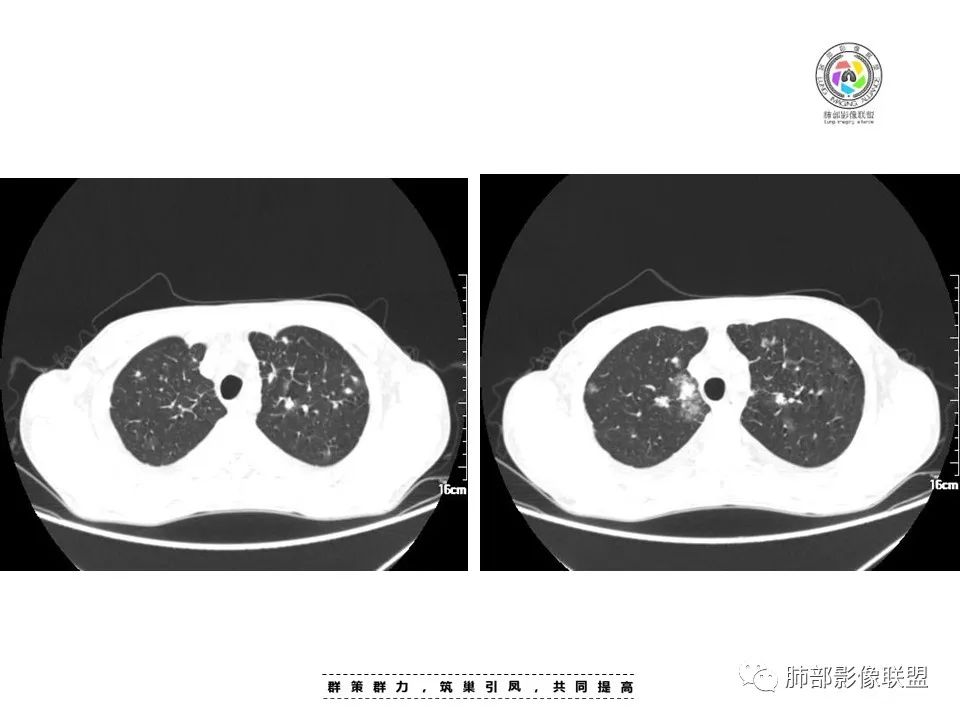

2022.8.29晚读:病例1

男,45岁

病史:发热、纳差、乏力、皮疹1月。T38.4℃,,全身散在暗紫色丘疹。CD8高,CD4低。CA-125略高。

两肺弥漫性性结节状、小片状及片状带晕的病灶,煎蛋征、点晕征,主要分布两肺中下叶,病灶周围小叶间隔增厚呈网格状影,部分病灶累及胸膜,伴两侧胸膜增厚。

印象:

真菌性肺炎,弥漫性病变,形态多样,混合晕征。

病毒性肺部感染,表现为肺部晕征及点晕改变。

血管炎:病灶累及下血管,肺泡及腺泡填充,周围渗出,代表出血,并累及气道。ANCA相关性的血管炎,包括GPA、MPA和EGPA,结合临床全身散在暗紫色丘疹,可以考虑。

肿瘤性病变:转移瘤?淋巴瘤?等

2.本例双肺小叶间隔增厚明显,多发结节影及片状实性密度影,沿血管支气管束分布为主,两侧较为对称,病灶多环以磨玻璃晕,边界不清。

双侧胸腔少量积液。双肺门及纵隔未见明确肿大淋巴结,纵隔结构间隙模糊。

1.结节型:两肺沿支气管血管束分布的结节影,呈火焰状或星芒状、挂果征,局部周围出血磨玻璃影(肺泡出血或水肿)。

2.支气管血管束增粗型:

肺门周围支气管壁呈“套袖样”改变。

3.肺炎渗出型:

斑片渗出影,部分融合呈“火焰样”,同时有火焰样结节,小叶间隔增厚等表现。

还可以有纵隔及腋下淋巴结增大,胸腔积液等表现。